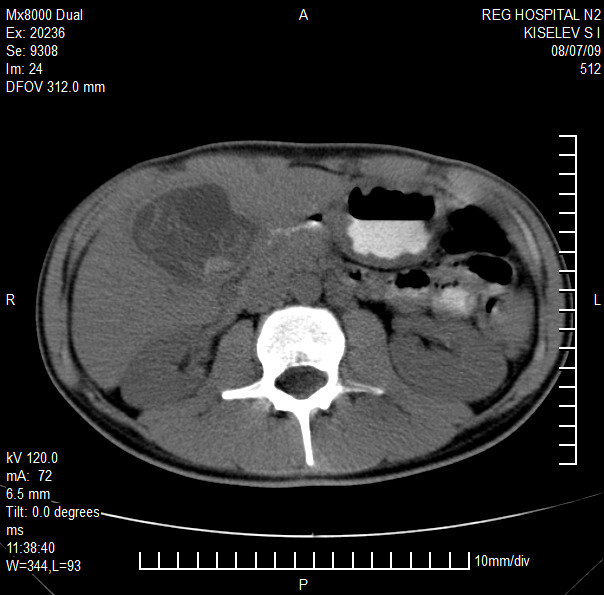

Представлены клинические наблюдения редкого осложнения эхинококкоза печени – прорыва эхинококковой кисты в желчные протоки. Осложнение стало причиной обструкции желчных протоков, механической желтухи и холангита. Освещены этапы диагностики, роль УЗИ в выявлении осложнений эхинококкоза печени, рассмотрены способы минимально инвазивного лечения с применением эндоскопических и чрескожных технологий под контролем лучевых методов.